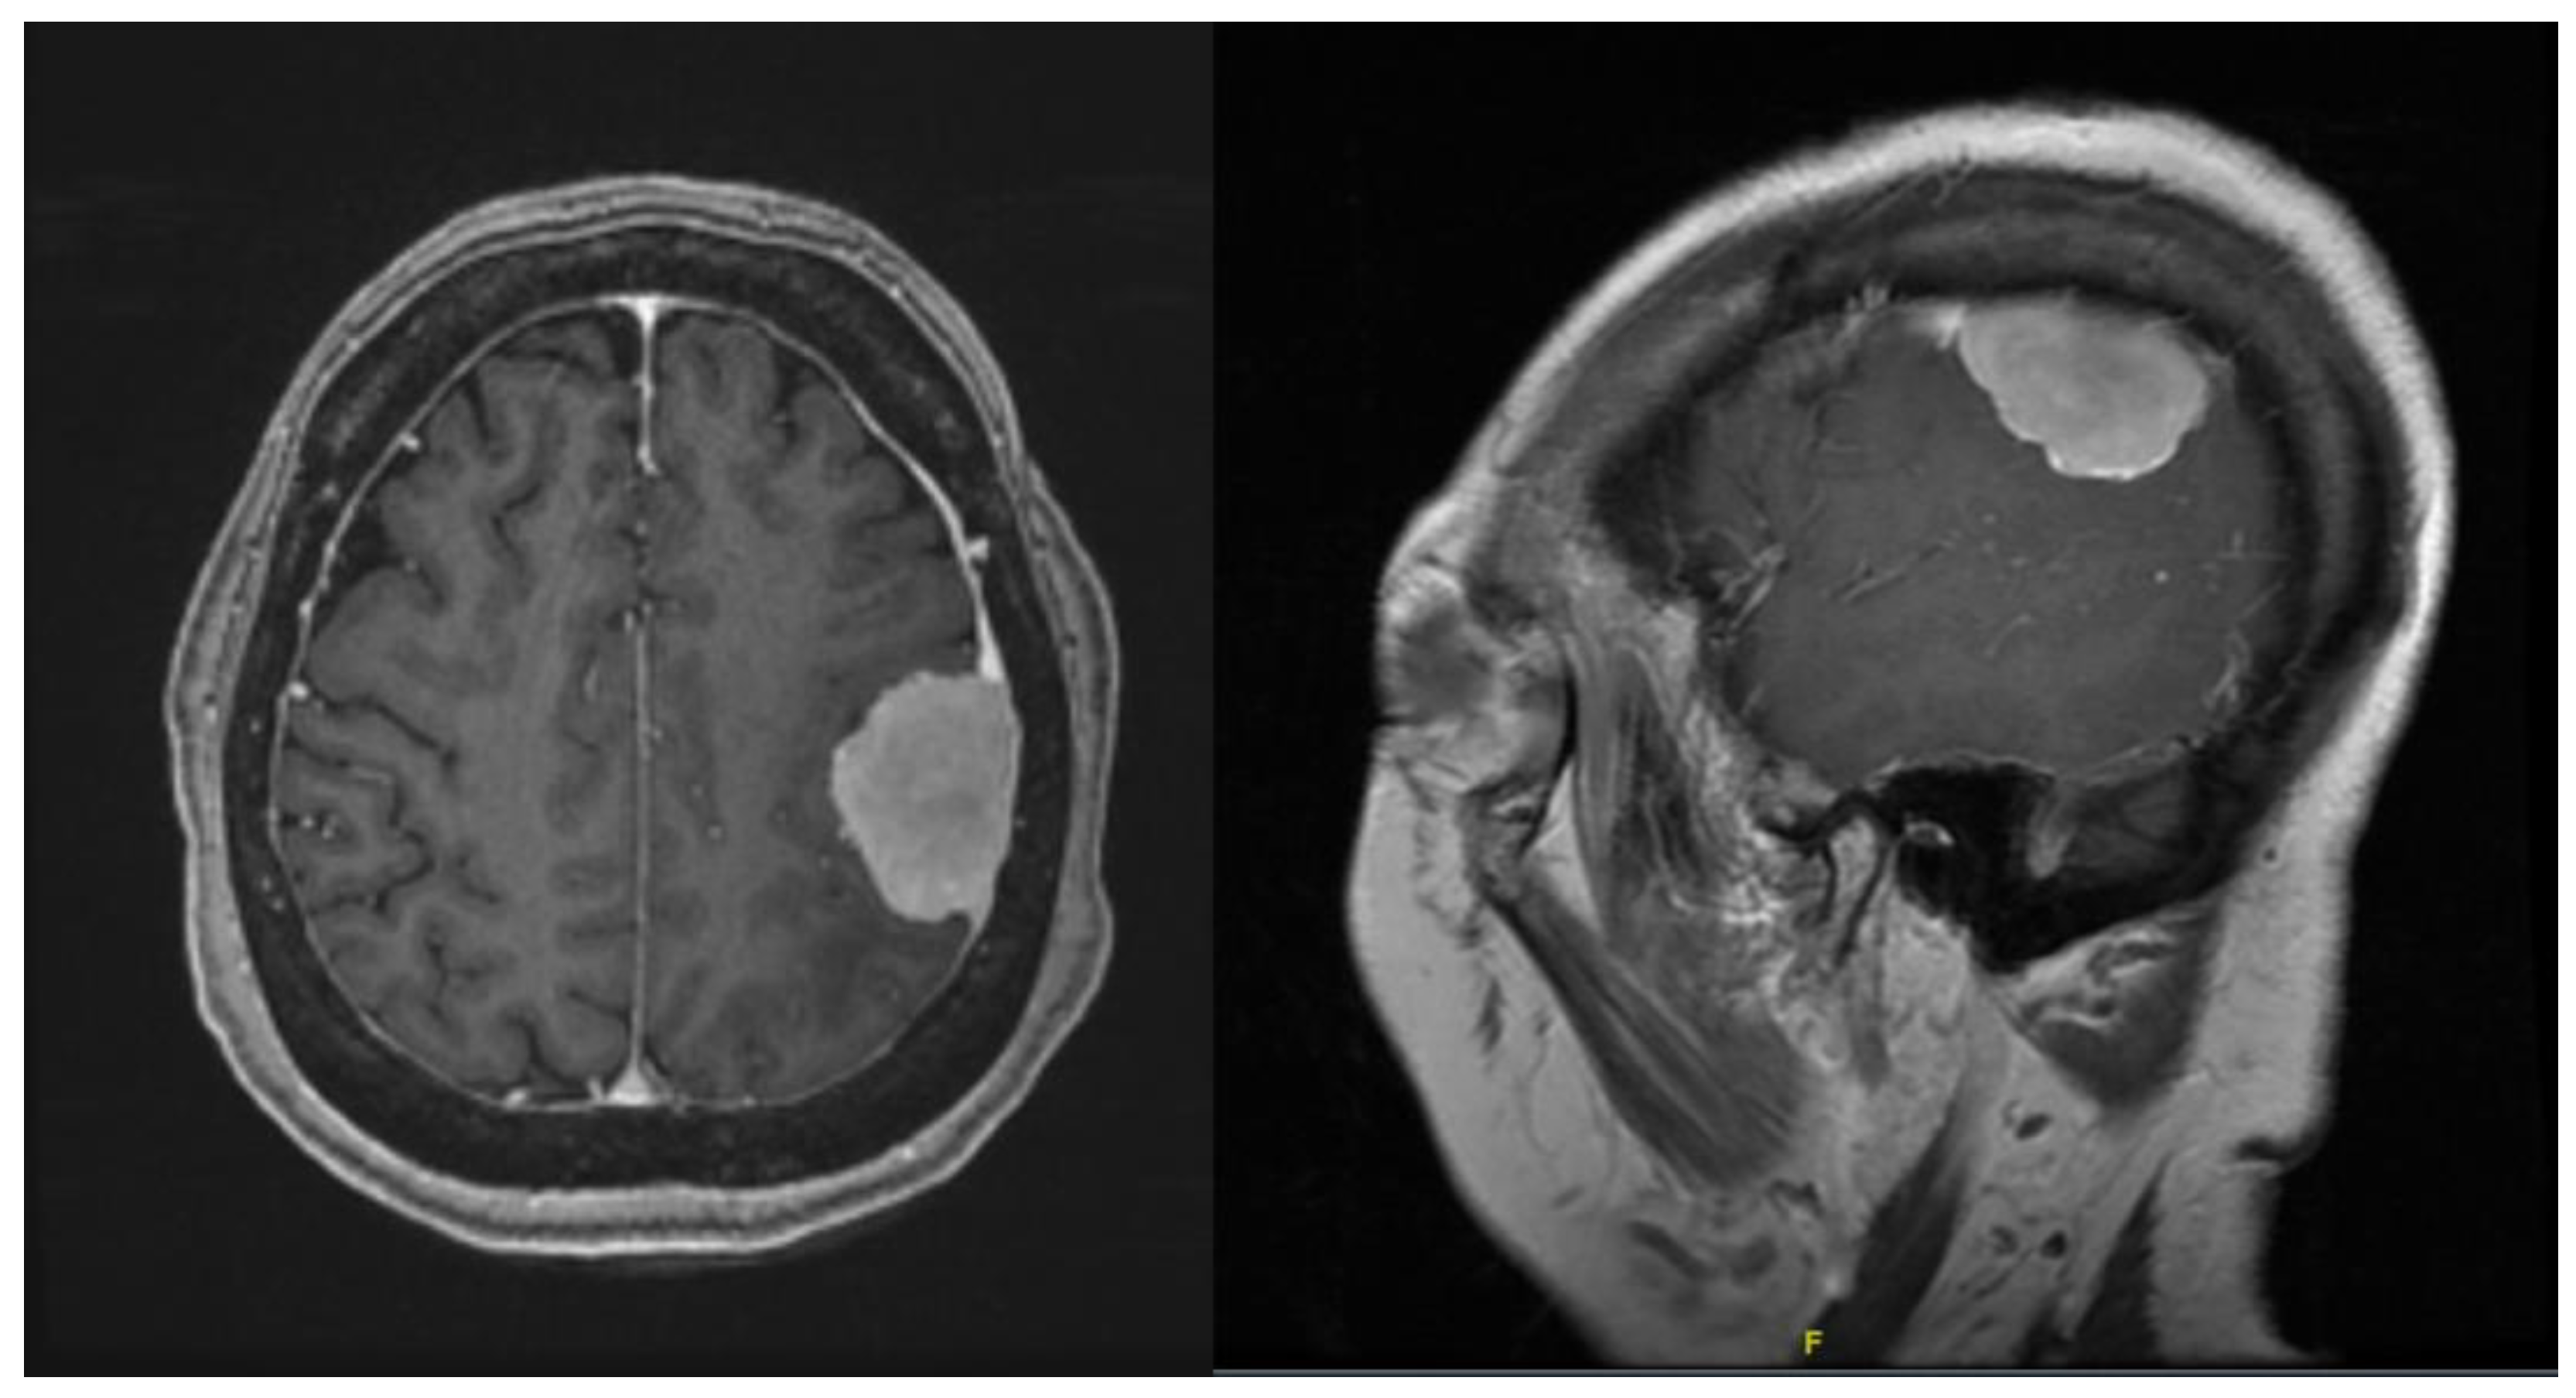

The first patient was a 72-year-old female with known history of right occipital parafalcine meningioma. The histology was consistent with that of atypical meningioma, WHO grade II. During follow up, she was noted to have recurrence of the lesion at the surgical bed, 1.5 cm in maximum diameter (Figure 1). The patient agreed for surgical resection of the lesion. As shown in Figure 1, patient’s tumour was deep seated, and an accurate neuronavigation was required to ensure that the tumour was resected. Standard neuronavigation MRI images were obtained for intra-operative planning. These images were then uploaded onto the HoloLens 2 system for rendering into a 3D image.

Figure 1. Contrasted T1 MRI: (a) sagittal, (b) coronal, and (c) axial planes showing recurrence of the lesion at the surgical bed, 1.5 cm in maximum diameter.